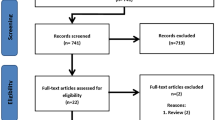

A primary literature search was conducted by our medical librarian with the aim of identifying any studies performed within the last 15 years that examined the use and effect of PSI on deformity correction procedures of the proximal femur or pelvis. This search was limited to paediatric patients and had no language restriction given the limited number of articles available. Our search was conducted using Ovid Medline, Ovid Embase, and CENTRAL, as well as WebOfScience and clinicaltrials.gov for unpublished/grey literature. An example of our search string used in Ovid Medline (reference) can be found in Additional file 1: Appendix 1. Our predetermined inclusion criteria were patients with pelvic or proximal femoral deformity/lesion, use of PSI, femoral/pelvic application of PSI, within 15 years. Exclusion was based on application of PSI to arthroplasty of the pelvis or femur, and their use in adult patients. Our search of the above databases produced 1143 studies. After removal of duplicates and non-paediatric based papers, 226 papers remained. Two independent reviewers, using the predetermined selection criteria, performed title/abstract review and found 20 studies appropriate for full text review. The same reviewers independently performed full-text review and found 10 studies for final inclusion and analysis. Any differences were resolved by consensus after discussion. Figure 1 outlines our study selection. Each selected study was graded for level of evidence using the Oxford Center for Evidence Based Medicine Levels of Evidence Guidelines [2]. Data extraction was performed manually, and included effects on operating time and intraoperative image use, as well as osteotomy, screw positioning, and general clinical outcome. Data were combined in a narrative synthesis; a meta-analysis was not performed given the diversity of study designs and interventions examined. Characteristics of included studies can be found in Table 1.